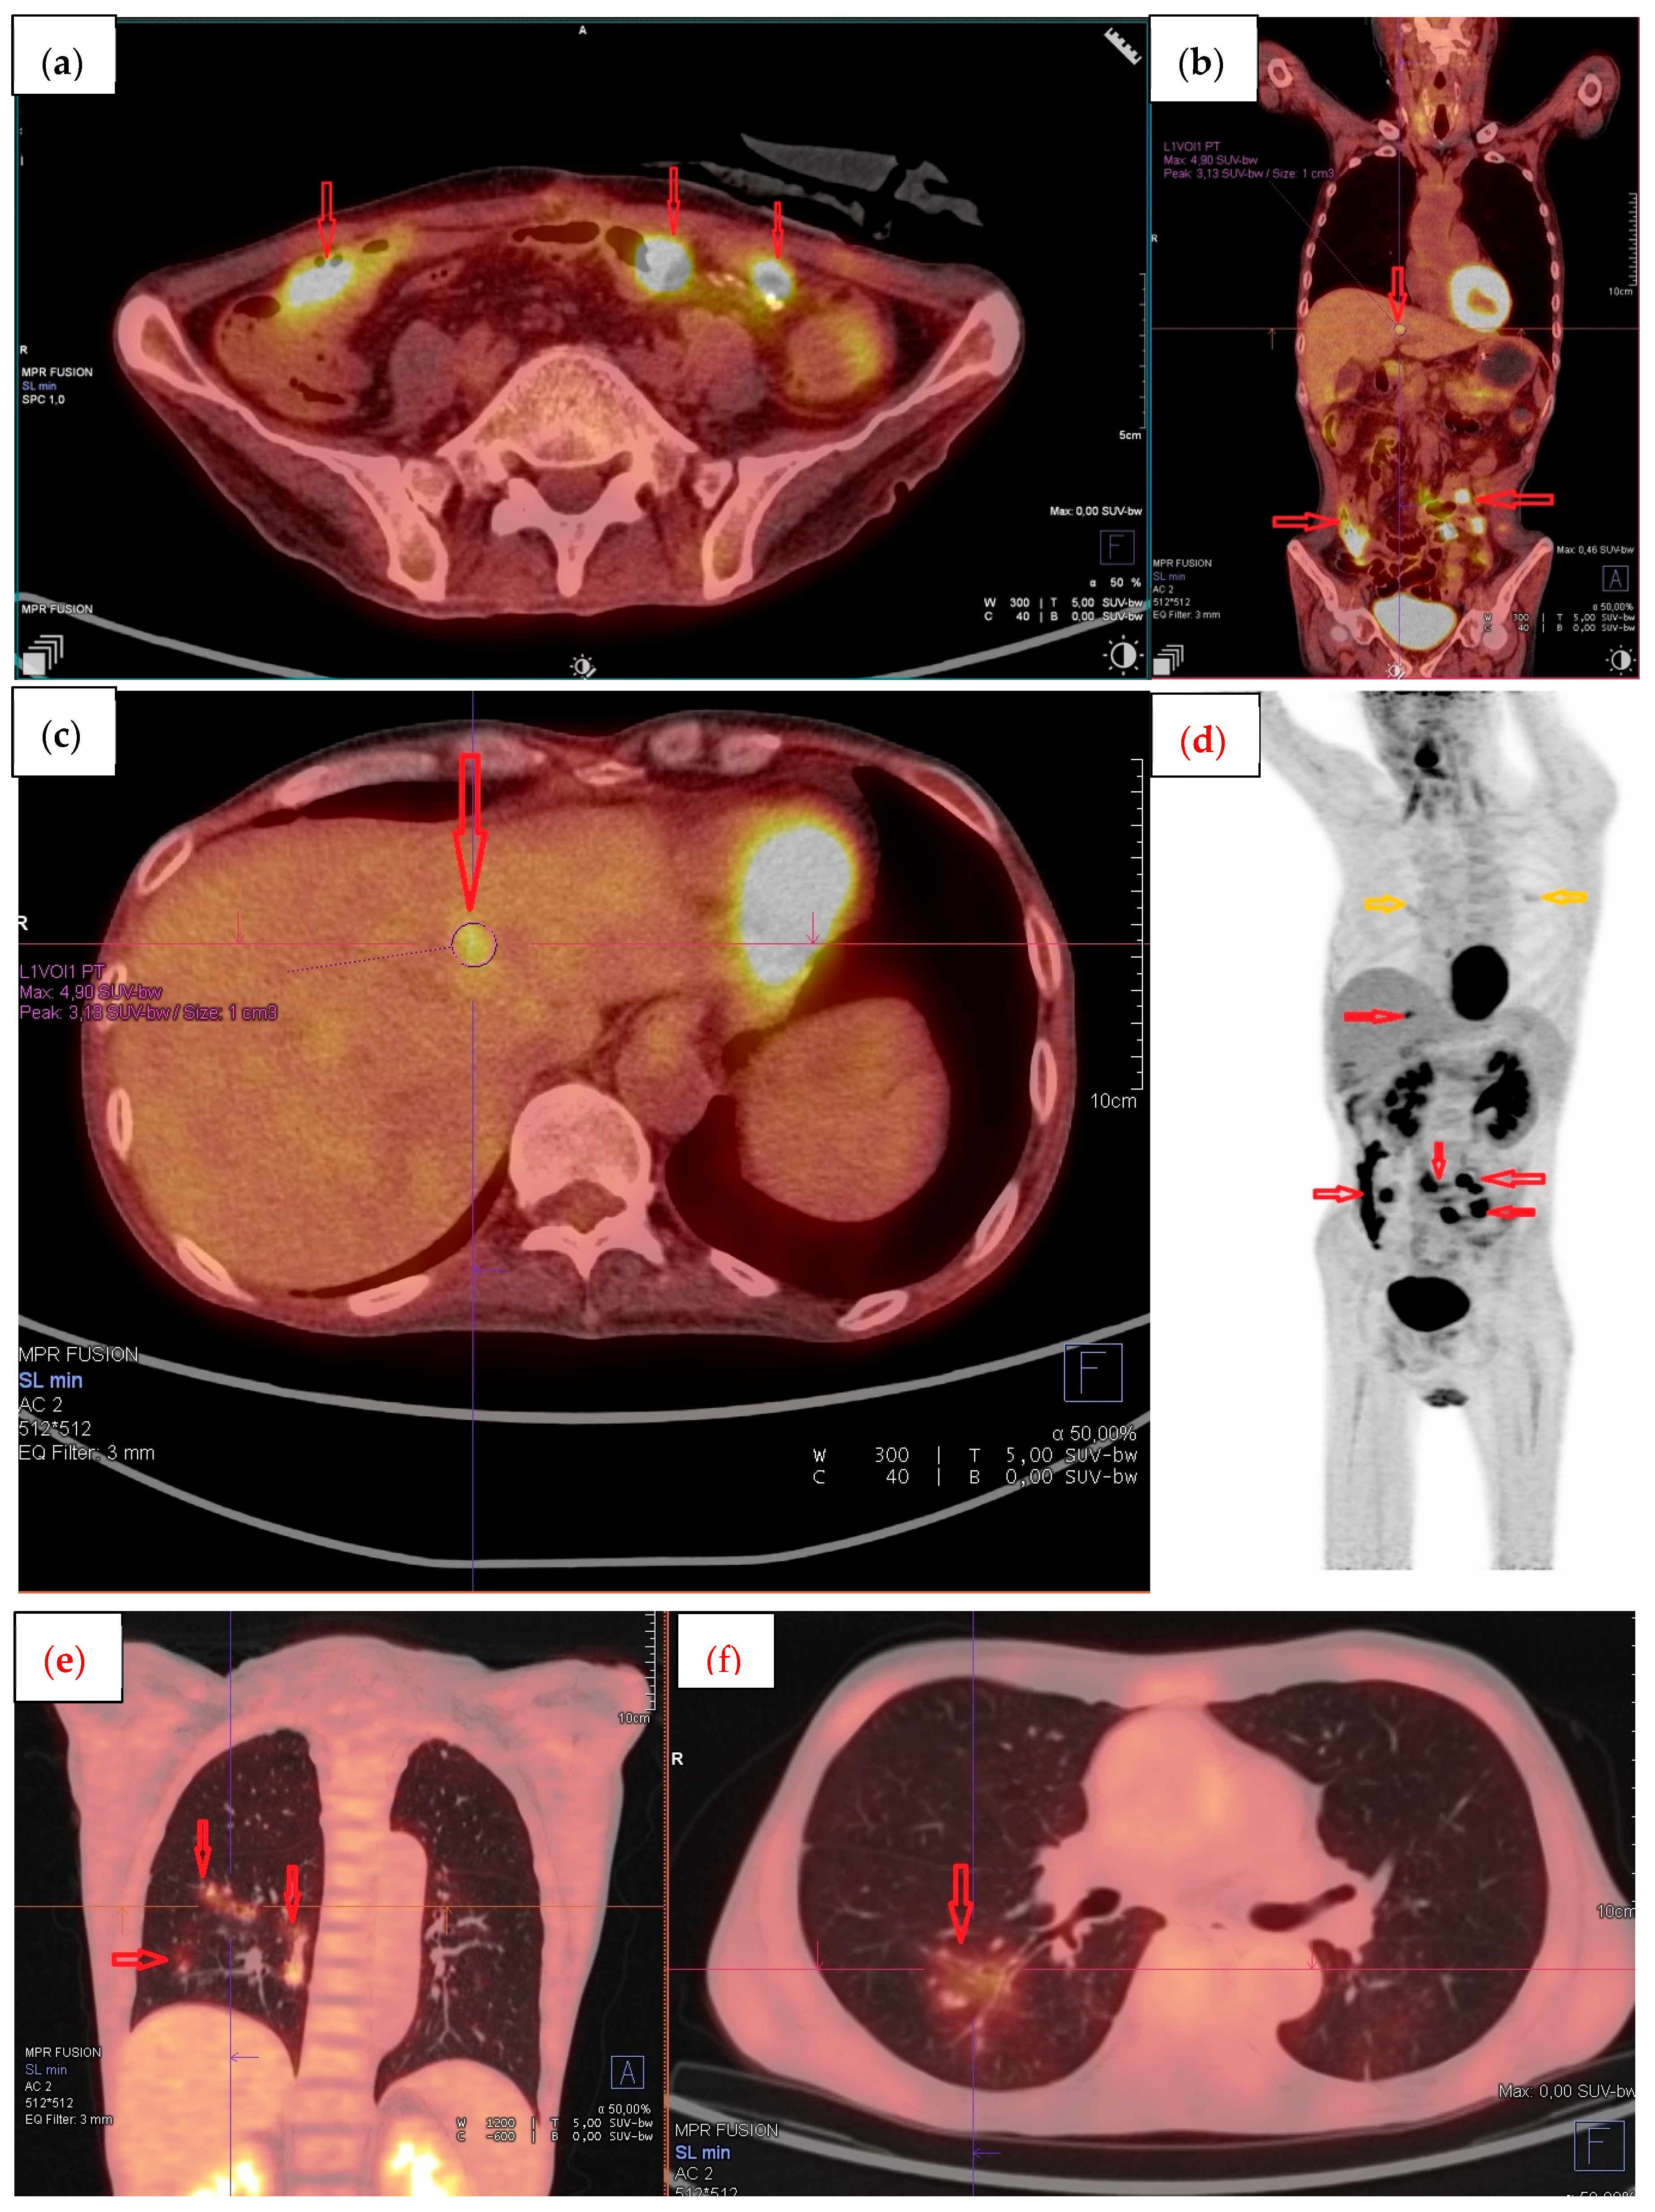

2. Case Report